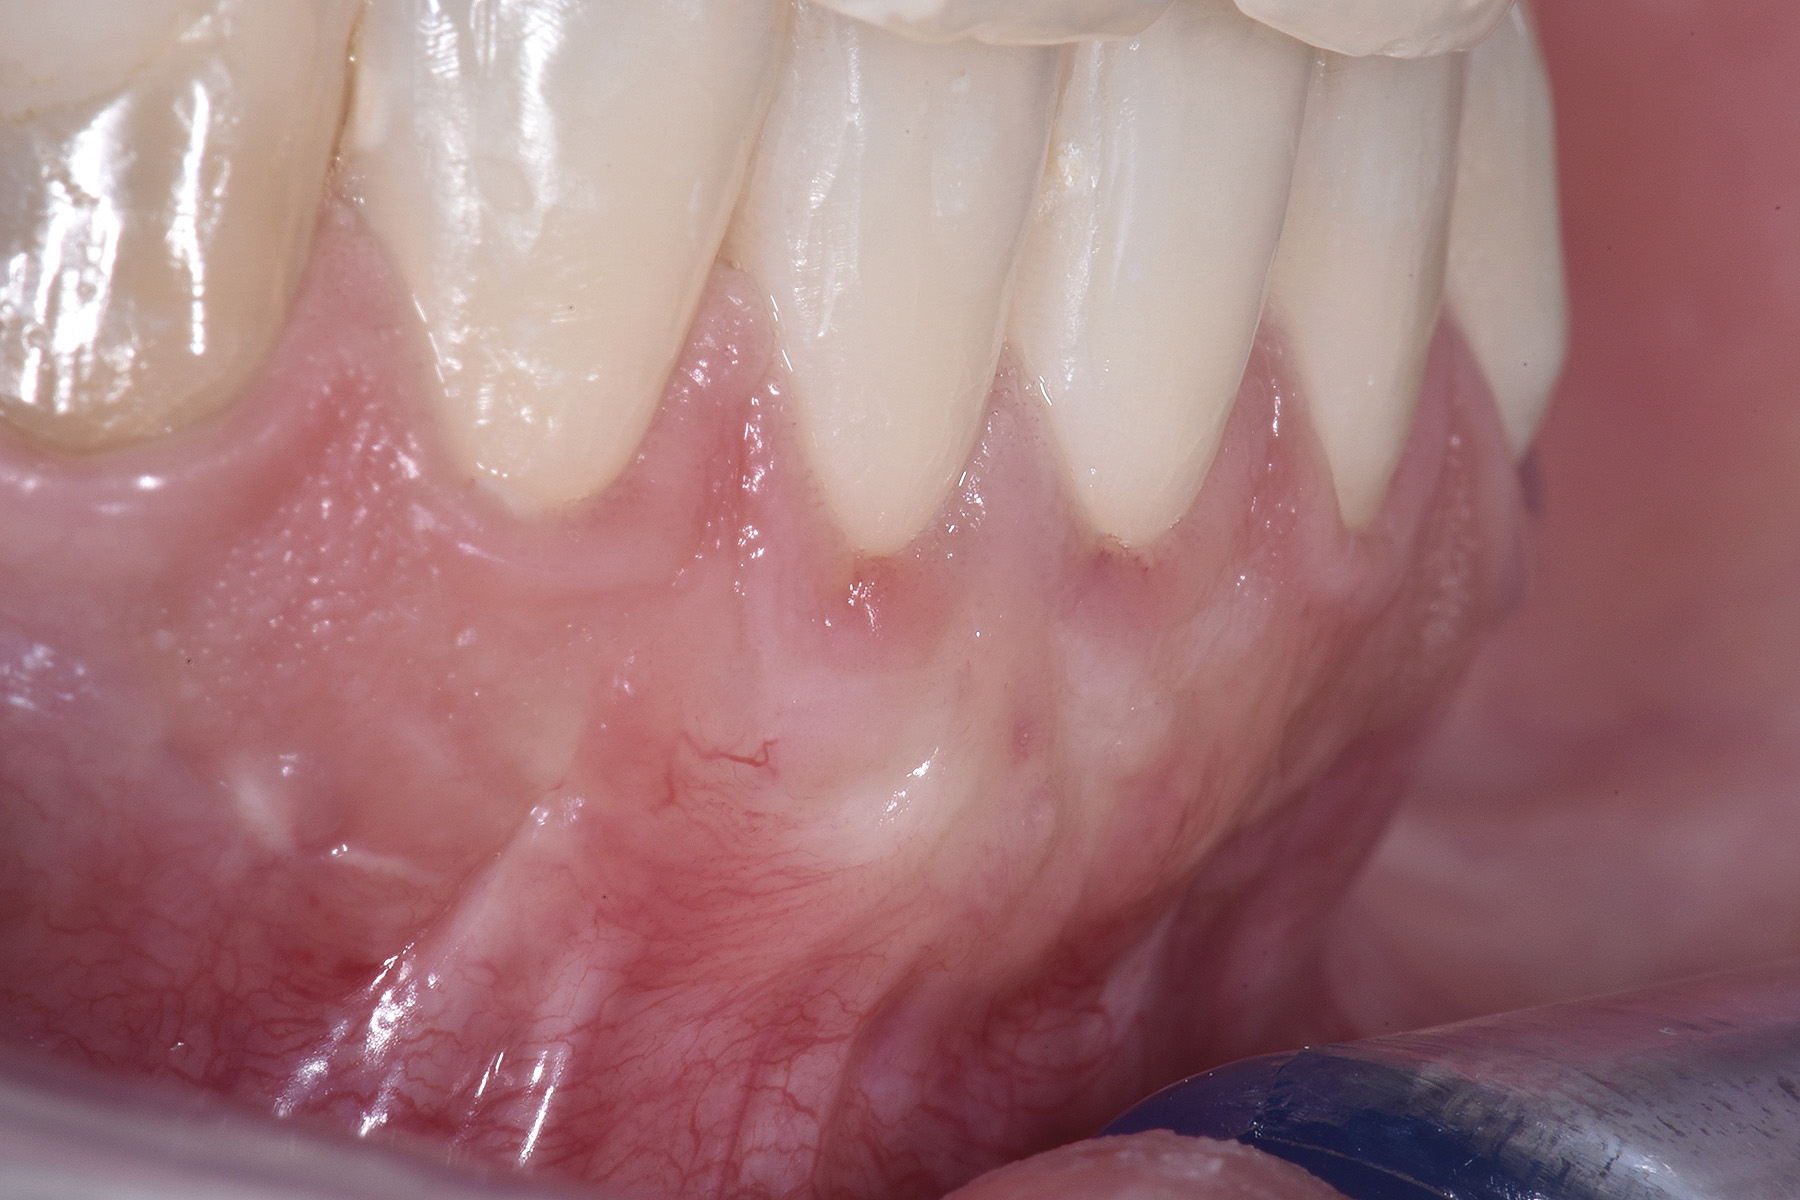

PREMESSA: in seguito all’estrazione dell’incisivo laterale superiore di destra, resasi necessaria per cause batteriche, si decide di affrontare il caso con il posizionamento di un impianto in sostituzione dell’elemento mancante dopo guarigione del sito infetto. Con tecniche rigenerative sia dei tessuti ossei mancanti a causa dell’infezione pregressa, sia dei tessuti gengivali che appaiono inizialmente troppo spostati in alto, si ripristina una corretta morfologia delle parabole (contorni) gengivali e delle papille interdentali (triangoli di gengiva tra due denti vicini).

Vengono utilizzati 2 tipi di provvisori: il primo, cementato ai denti vicini, viene utilizzato dal momento dell’estrazione del dente fino ad impianto osteointegrato (circa 6 mesi); il secondo, avvitato direttamente all’impianto, ha una funzione di prova estetica ma soprattutto di guida per la maturazione dei tessuti gengivali peri-implantari portandoli verso la maturazione completa prima di posizionare la corona finale in disilicato di litio.